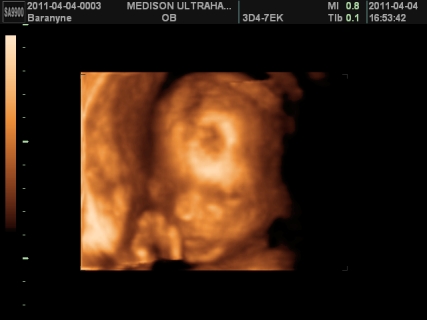

gyerek témában is helyretettem magam, ennek is tök egyszerű oka van, FÉLEK TŐLE. ezen nem változtat az idő, ha 1 év mulva mennék ,akkor is félnék tőle. sajnos nekem nem életem legszebb élménye volt a várandóság, én tényleg terhességként éltem meg. egyszerűen annyi a szabadságomnak, mert szinte mindenről le kell mondanom, bár remélem most nem így lesz meg. ámulva hallgatom, akinek a legszebb élmény a várandóság volt. valamilyen szinten nekem is, de csak mikor kiderült ,hogy sikerült és mikor megszületett boti, a többi rész kihagynám, mert nem tudtam önfeledten örülni sem az első szívhangnak, sem az első uh-nak, mert mindig bennem volt a félsz. ezt talán legjobban bibó értheti meg. viszont nagyon nagyon szeretnék egy kismanót, de egyszerűen nem tudom elképzelni, hogy hogy fogom tudni boti mellett megoldani. anyuékhoz sem passzolhatom le mindig botit, ha mondjuk fáradt leszek, vagy isten ne adja vérzek. mi lesz vele? na ezen ráérek agyalni, de már nem sokáig, mert kb 3 hét és visszaülti. bár tudnék felhőtlenül örülni, de a félelmemet nem tudom leküzdeni. alig várom ,hogy jöjjön a kisboti